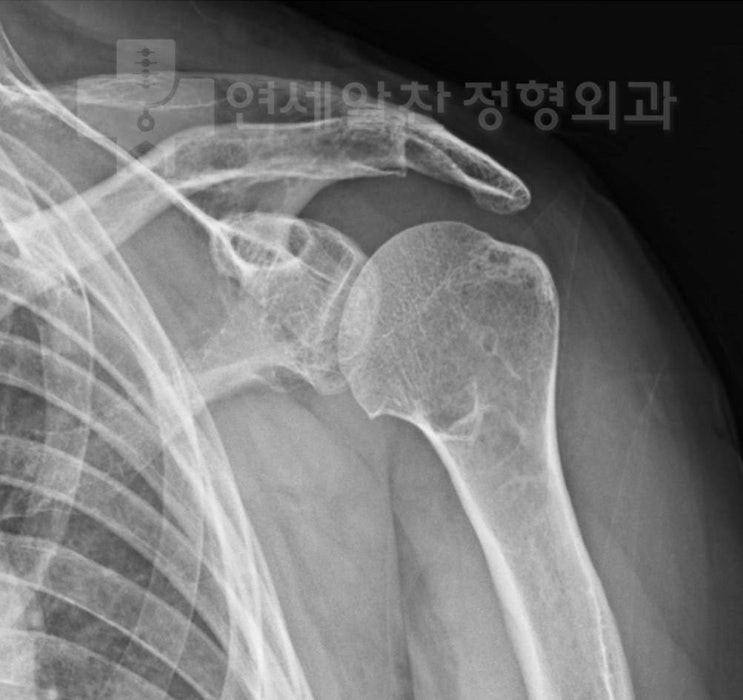

Abrasion Arthroplasty and Rotator Cuff Repair for Rotator Cuff Tear with Shoulder Osteoarthritis

#shoulder osteoarthritis#rotator cuff tear#abrasion arthroplasty#rotator cuff repair#arthroscopy